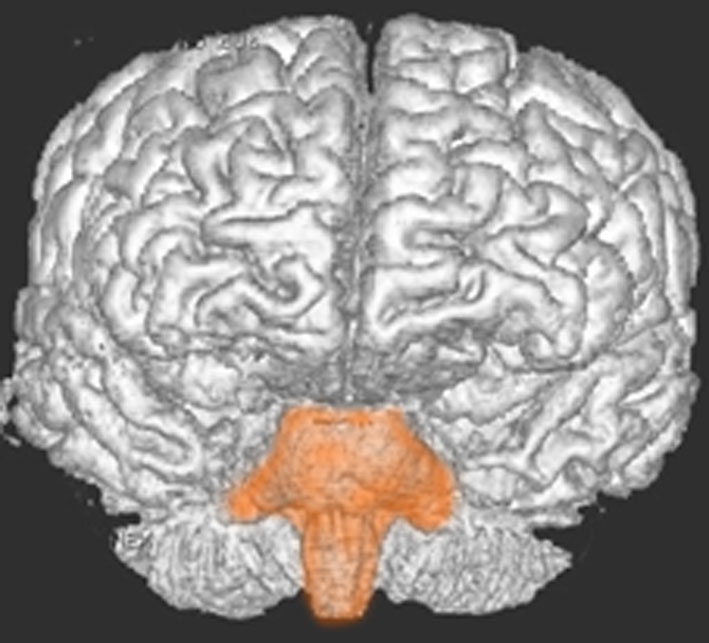

脳幹部の解剖図

- 脳の底面からしか見えないのでいろいろな角度から見ています